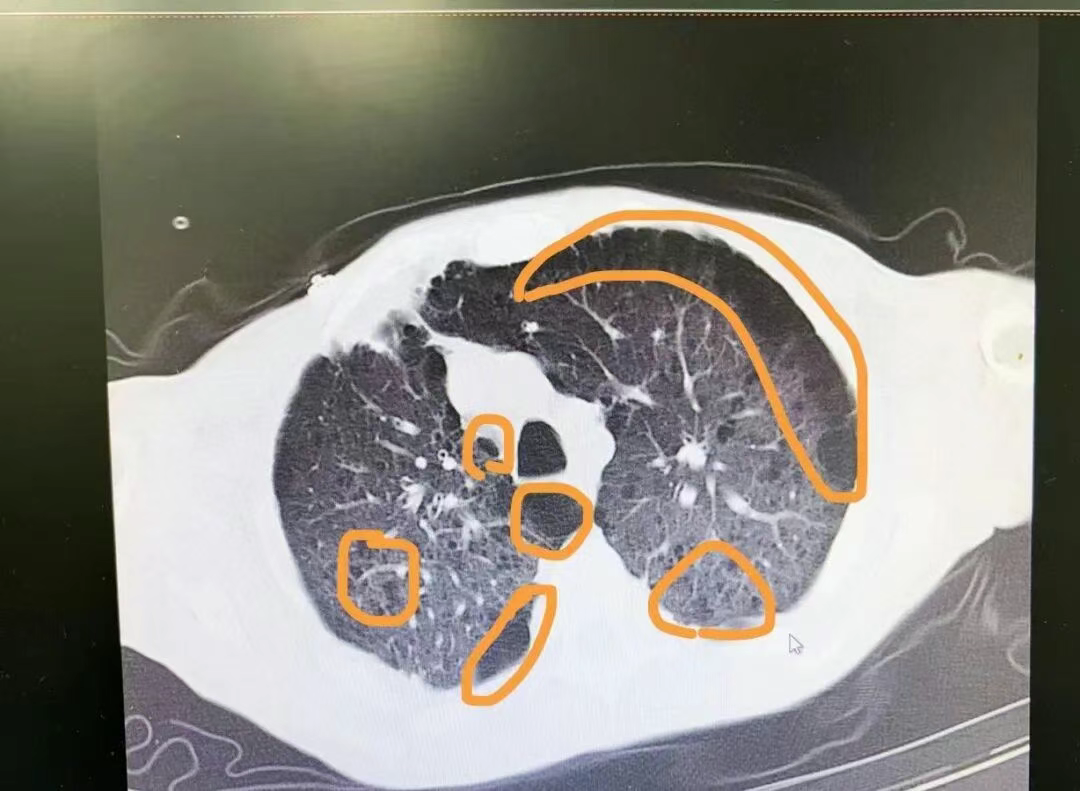

(↑↑ 这是一位因吸烟导致肺气肿病人的CT影像,黄色圈圈内发黑的部分都是病变的肺组织。)